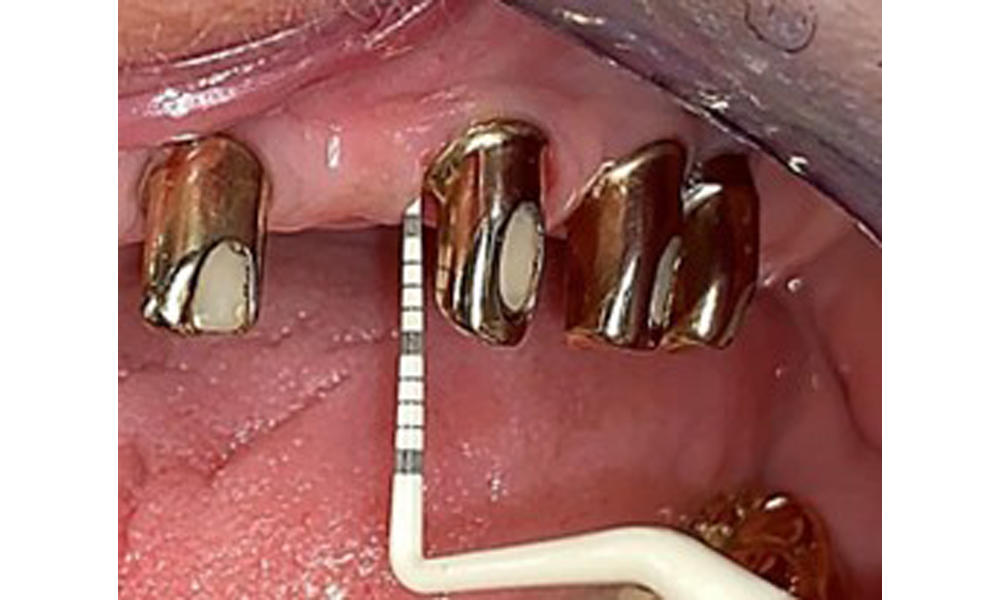

Der dentale Befund stellt sich wie folgt dar: Kombinierte herausnehmbare Implantat- und zahngetragene Teleskoparbeit auf Implantaten 15, 13, 21, 23, 24, 25 und Zahn 11 (Abb. 1, Abb. 2, Abb. 3). Im Unterkiefer ist die Patientin mit einem festsitzenden Zahnersatz versorgt. 37–34 sowie 45–47 haben suffiziente Brücken (Abb. 4). Kronenränder sind intakt, aktive kariöse Läsionen sind nicht vorhanden. An Zahn 43 zeigt sich eine Compositefüllung mit Randspalt. Im Unterkiefer liegen Rezessionen mit freiliegender Wurzeloberfläche zwischen 1 – 3 mm vor. Dies trifft auch für 11 zu.

Okklusalansicht: Oberkiefer mit Zahn- und implantatgetragenen Teleskopen.

Abb. 2: Okklusalansicht: Oberkiefer mit Zahn- und implantatgetragenen Teleskopen.